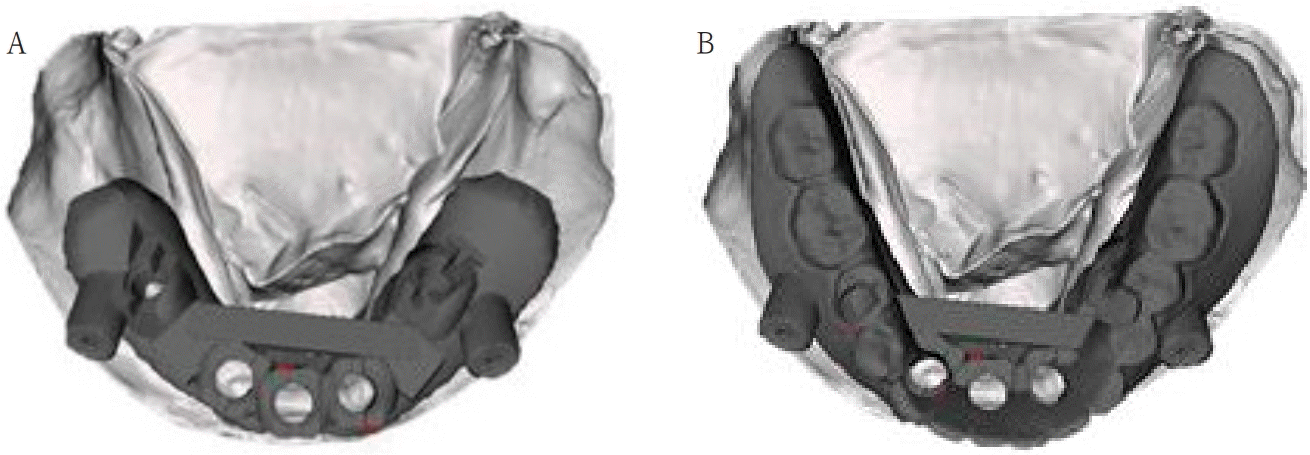

Fig. 8.

A. Under part of surgical guide with fixation pin is situated on dental stone cast. B. Upper part of surgical guide is overlapped with under part.